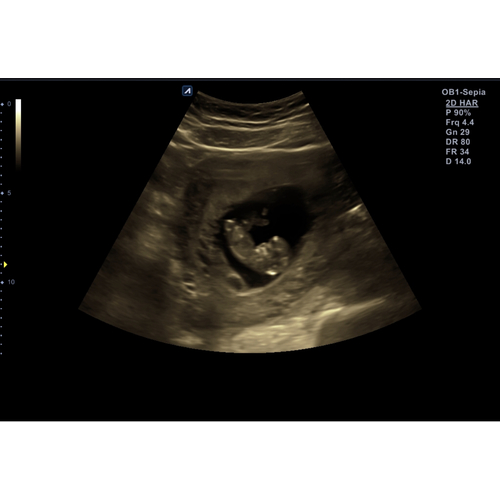

Nieuwsgierig 💖💙... nub 3 werd gesloten🤪..

Renate 33 meisje :)